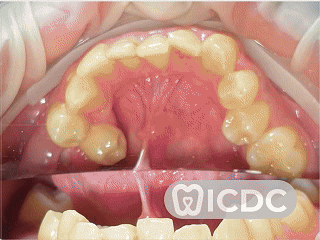

เคสนี้คนไข้มีฟันเขี้ยวด้านบนฝังอยู่ใต้เหงือก หมอวางแผนถอนฟันน้ำนมออกและดึงฟันที่ฝังอยู่ด้านใต้ขึ้นมาครับ